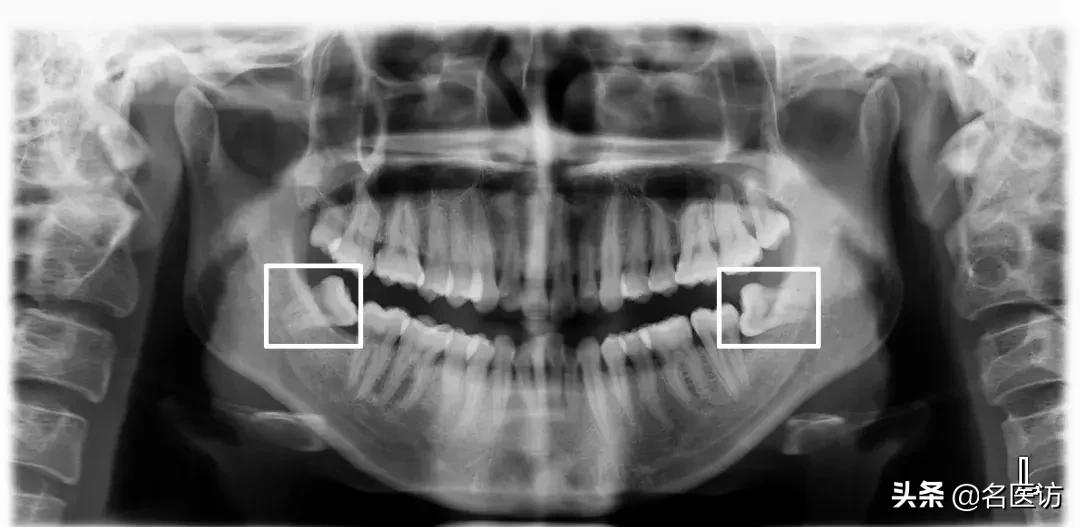

2、牙齿异常

阻生牙、埋伏牙和恒牙的先天缺失是错颌畸形的原因之一。阻生牙常压迫相邻牙齿并导致相邻牙齿牙根的吸收,而阻生的第三磨牙(俗称智齿)如果没有在矫正前拔除,很可能会成为日后牙齿问题复发的罪魁祸首。

阻生牙